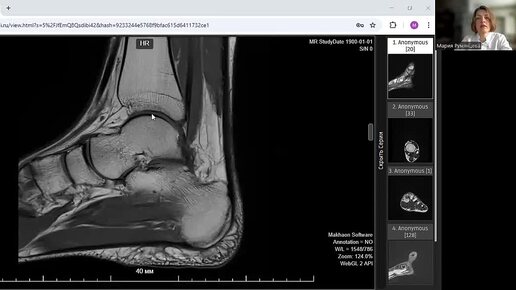

МРТ голеностопного сустава норма